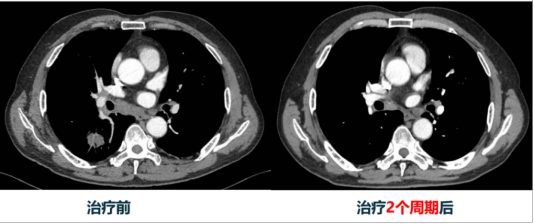

完成两周期治疗后,苗先生病情有了显著好转。胸部CT显示肺部肿瘤明显缩小,实性部分基本消失变成了多房空洞;最大的转移淋巴结从2.3cm缩小到1.5cm;之前升高的肿瘤标志物中多项已恢复正常。咳嗽、胸闷等症状明显减轻,生活质量大大提高。目前,苗先生正按计划继续随访治疗。